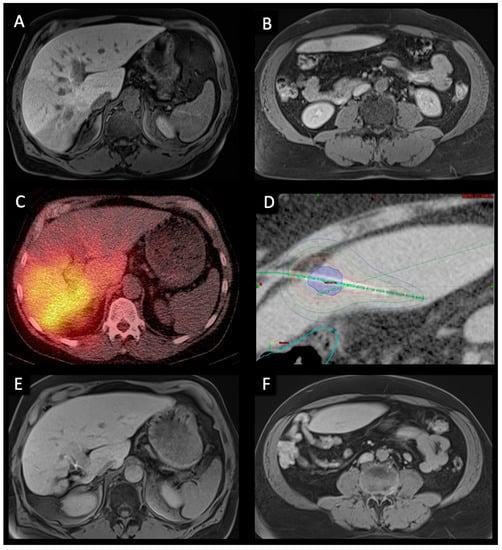

2.1. CT-HDRBT

2.2. TARE